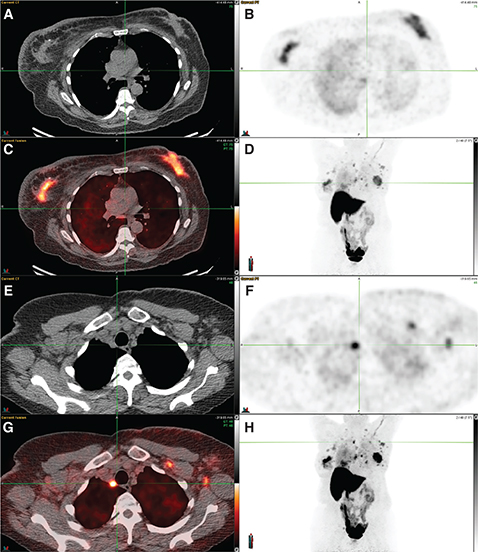

Fig 2

Figure 2. 18F-FES PET/CT in carcinoma breast. 18F-FES PET/CT in a patient with initially diagnosed left breast invasive ductal carcinoma (IDC), cT1cN0, ER+/PR+/HER-2 negative, Ki67 11%. Initially declined treatment and now with bilateral breast masses with Ki67 20%, bilateral lymphadenopathy, and pulmonary nodules. Images include: (A) axial CT, (B) axial FES PET, (C) fused axial PET/CT, (D) maximum intensity projection (MIP) image, (E) axial CT, (F) axial FES PET, (G) fused axial PET/CT, and (H) MIP image. 18F-FES PET/CT demonstrates increased FES uptake in the bilateral breast masses (images A-D), lymph nodes in the bilateral axillae, subpectoral regions, and mediastinum (images E-H), and bilateral pulmonary nodules (lung windows not included).